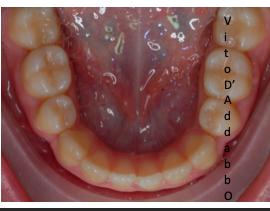

dopo – fase 2